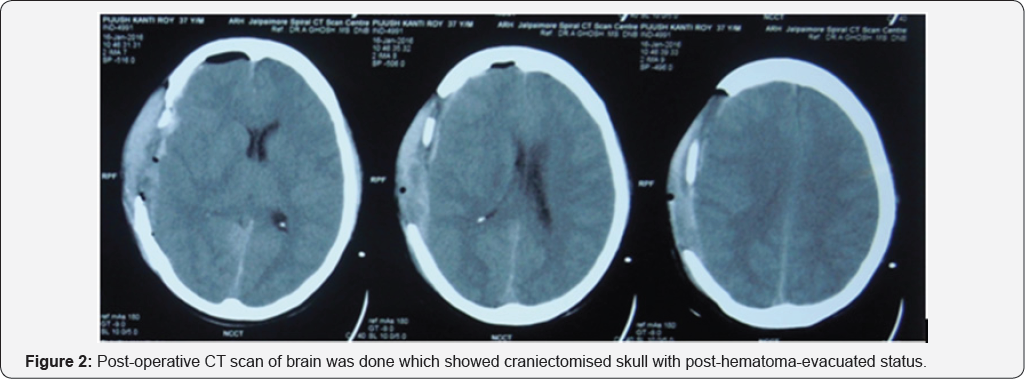

Post-operative CT scan of brain was done which showed craniectomised skull with post-hematoma-evacuated status (Figure 2).